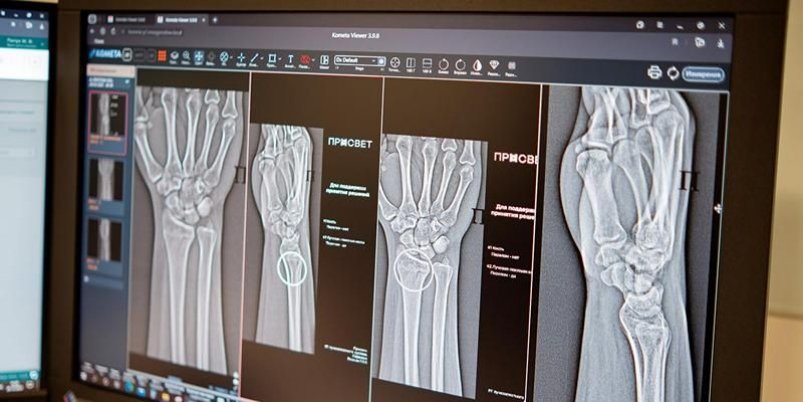

ИИ-ассистенты для диагностики сложных травм начали работать в клиниках Москвы

StolicaMedia, 18 ноября 2025. Две новые системы на основе искусственного интеллекта начали работать в медучреждения Москвы. Они способы с высочайшей точностью выявлять сложные травмы опорно-двигательного аппарата. Об этом сообщается на сайте mos.ru.

Как рассказала заммэра Москвы по социальным вопросам Анастасия Ракова, в арсенале столичных рентгенологов появились два новых ИИ-сервиса. Они специализируются на диагностике множественных переломов голеностопного и лучезапястного суставов. Как отметила Ракова, эти части тела относятся к числу наиболее функциональных и одновременно уязвимых элементов скелета.

"Алгоритмы автоматически отметят поврежденные участки и выполнят необходимые измерения, даже если на снимке присутствуют признаки сразу нескольких переломов", — сказала Ракова.

По словам главного внештатного специалиста по лучевой диагностике Москвы Юрия Васильева, новые технологии особенно востребованы при травмах предплечья, кисти и голени. По его словам, ИИ-алгоритм работает как интеллектуальный помощник, повышающий точность и скорость анализа изображений. Это позволяет оперативно назначить лечение и избежать осложнений.

Сегодня в распоряжении московских врачей находится уже более 60 различных ИИ-сервисов, которые применяются в 43 клинических направлениях. Одни системы отличают норму от патологии, другие — измеряют границы и размеры повреждений. В условиях массового потока пациентов такие технологические ассистенты помогают сохранять высокое качество диагностики для каждого обратившегося за помощью.